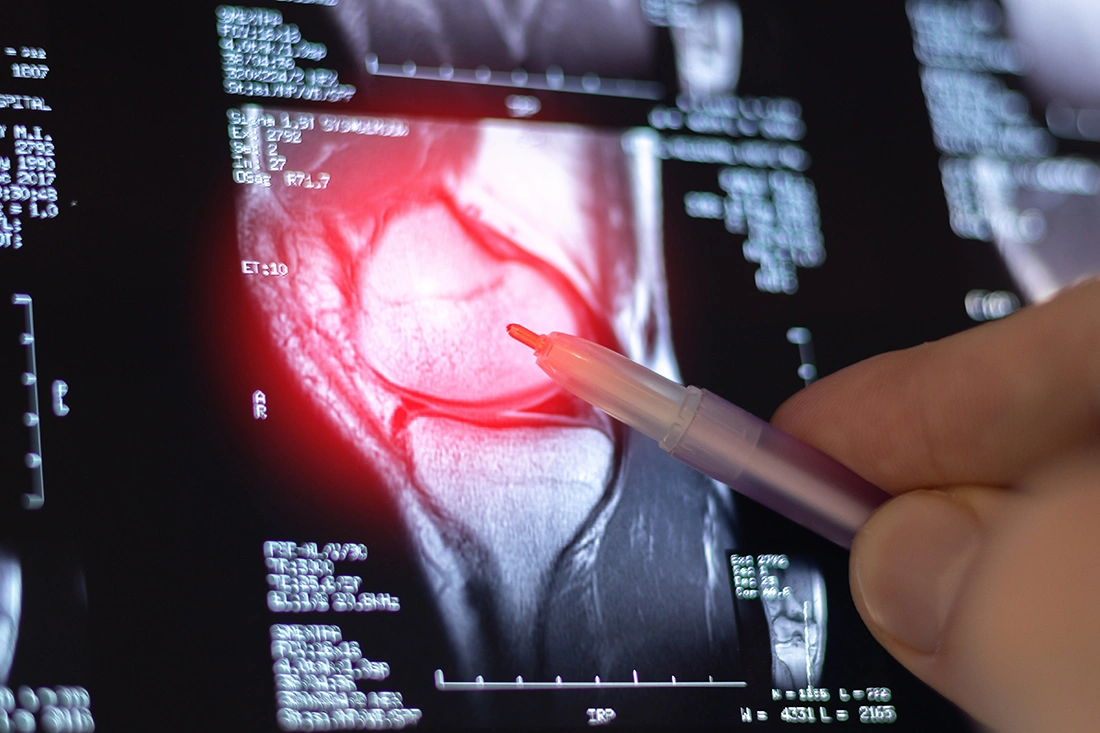

An MRI provides more detailed images of the soft tissues within the knee. This includes ligaments, tendons, cartilage and the meniscus. MRI scans are especially helpful in identifying injuries such as ligament tears, meniscus damage or other internal joint problems that may not be visible on an X-ray.

While MRI offers more detailed information, it is not always necessary as a first step. X-rays are often sufficient for initial assessment, with MRI reserved for cases where further evaluation is needed to confirm the diagnosis or guide treatment decisions.